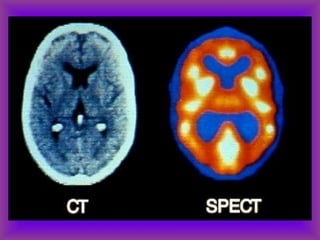

Uses for SPECT and PET

• Acute stroke

• Identify a seizure focus-increased

flow during sz and decreased

interictal flow

• Dementia-frontal pattern in FTLD,

temporo-parietal pattern in AD

• Ligand imaging in PD, others